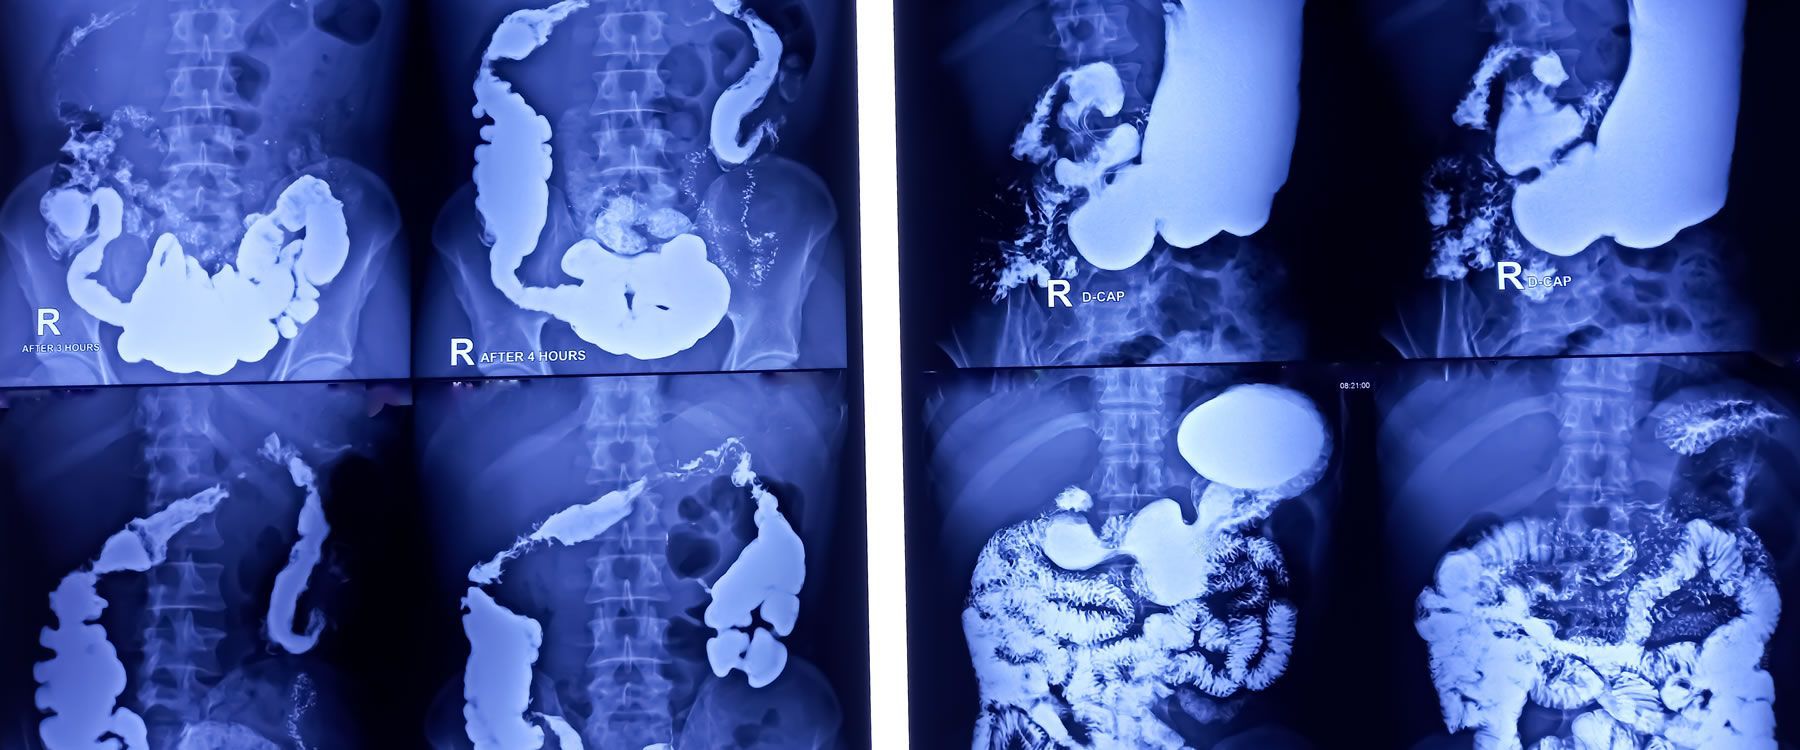

Fluoroscopy is a specialized type of real-time X-ray imaging that allows our Radiologists to see inside the body during a procedure. This technology improves precision, safety, and comfort during procedures, helping ensure the best possible results for our patients.

FLUOROSCOPY